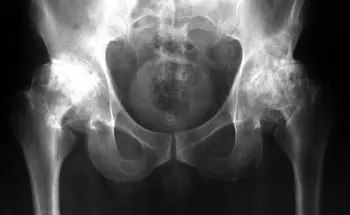

এই ছবিগুলো দেখো। সঠিক ছবিতে, জয়েন্টের জায়গা নেই, হাড়গুলো একে অপরের সাথে ঘষছে, যার ফলে তীব্র ব্যথা হচ্ছে। আর এই প্রক্রিয়া বন্ধ করা খুব কঠিন! কয়েক বছরের মধ্যে, ব্যক্তিটি অক্ষম হয়ে যাবে এবং নিজের যত্ন নিতে পারবে না।

এই সবই তরুণাস্থি টিস্যুকে নরম করে, জীর্ণ করে এবং পাতলা করে। প্রতিটি নতুন নড়াচড়ার সাথে, তরুণাস্থি জীর্ণ হয়ে যায় এবং বিকৃত হয়ে যায়, হাড়গুলি একে অপরের সাথে ঘষতে শুরু করে, যার ফলে অসহনীয় ব্যথা হয়।

রিউমাটয়েড আর্থ্রাইটিস এবং অস্টিওআর্থ্রাইটিস রোগ শুরু হওয়ার 3-5 বছরেরও কম সময়ের মধ্যে অক্ষমতা সৃষ্টি করতে পারে এবং আয়ু 15-20 বছর কমিয়ে দিতে পারে!